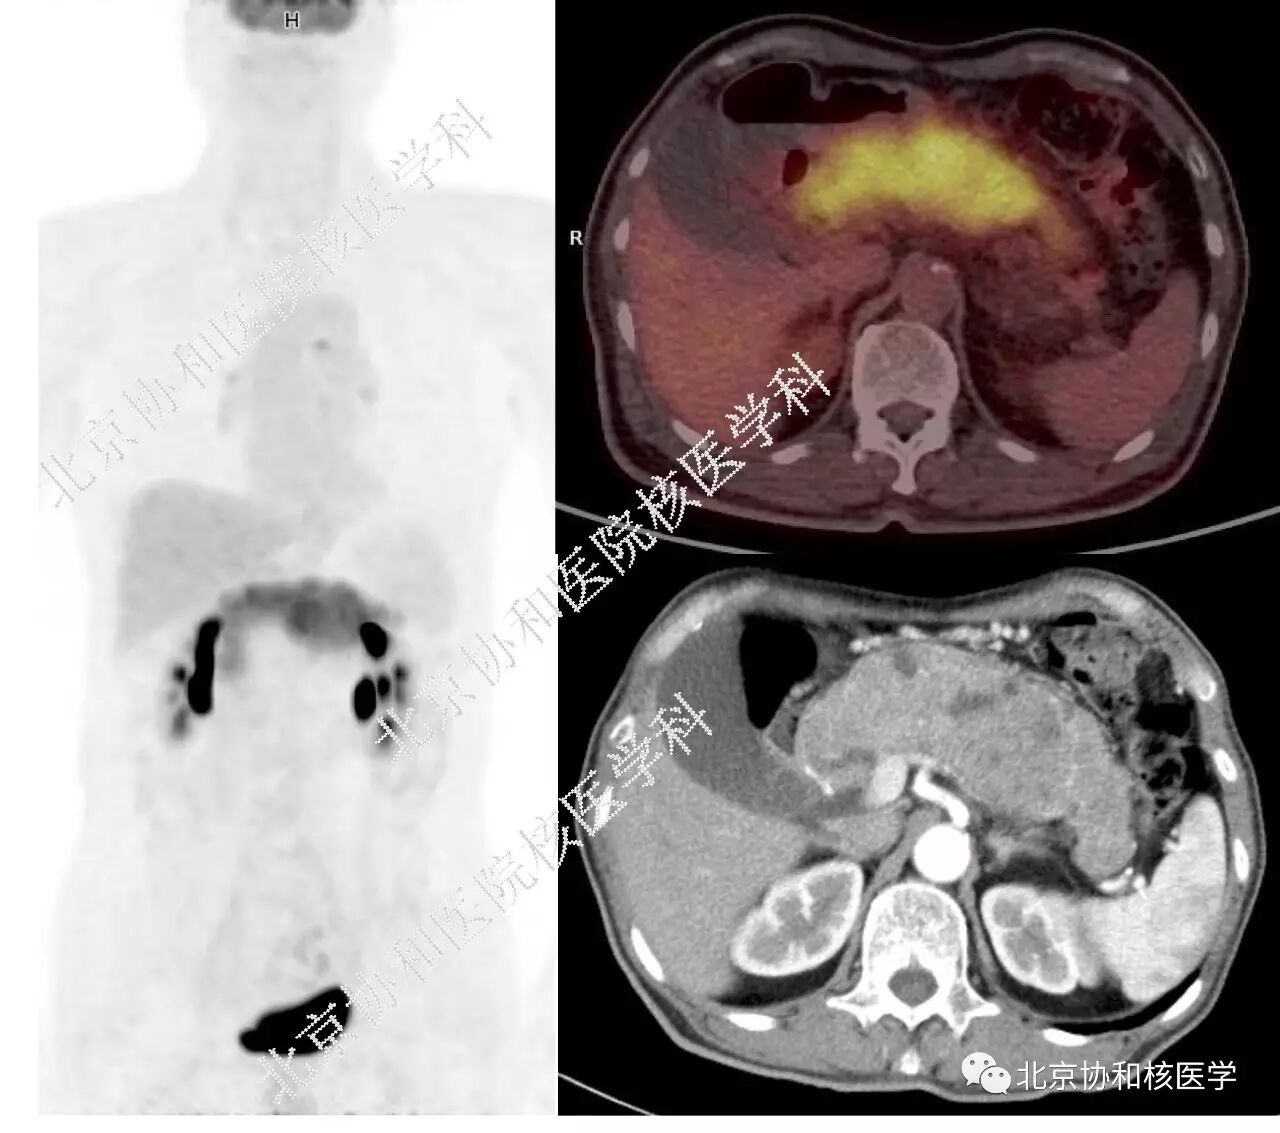

• 病例1: 老年男性,无症状,查体发现胰腺弥漫性肿大1年余。PET/CT见胰腺弥漫增粗,不均匀,代谢弥漫增高,自胰腺钩突弥漫累及至胰尾部。增强CT见胰腺肿胀,边界清晰,增强后不均匀强化,其中见多处小囊性变。

而本期病例1与其显著的区别是,病变虽然弥漫累及整个胰腺,但胰腺形态很不规则,胰体肿大更明显,增强CT也有多处囊变区域。这些表现虽然不能除外自身免疫性胰腺炎的诊断,毕竟胰腺全程受累、患者无症状、病程至少1年余并且临床无明显加重趋势,都比较支持是良性病变的诊断。但在这不典型的表现中,我们除了胰腺炎,还要考虑到少见情况下的胰腺弥漫性肿瘤的可能性,下诊断要更慎重。

病例1中患者之后行超声内镜引导下胰腺穿刺活检,诊断为胰腺腺泡细胞癌,特殊染色PAS(+),免疫组化AAT (+)AACT (+)AE1/AE3 (+)CgA (-)Syn (-)Vimentin(-)

最后我们来谈谈胰腺腺泡细胞癌为什么能够长成这样。胰腺腺泡细胞癌比较少见,只占胰腺外分泌腺肿瘤的1%-2%,临床上可无症状或表现为腹痛等非特异性症状,由于肿瘤对周围组织多为推压而非浸润,因此胰胆管梗阻少见,临床多无黄疸。影像学上通常表现为胰腺孤立性的结节或肿物,边缘光滑,有点类似胰腺实性假乳头状瘤的表现。胰腺腺泡细胞癌还有一种比较特殊的生长类型——导管内生长型,这种类型的腺泡细胞癌有时候可沿胰管播散,破坏胰管管壁并向周围胰腺实质侵犯。这种沿着胰管的特殊播散类型致使这种肿瘤可能弥漫累及整个胰腺,表现为胰腺弥漫肿胀、代谢增高[6-9]